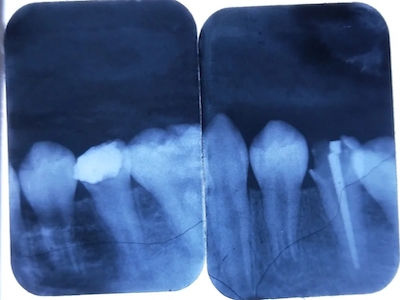

年轻恒牙龋指的是儿童萌出不久的第一恒磨牙龋病和上颌恒切牙龋病,其中第一恒磨牙龋病占年轻恒牙龋的90%,发病早,进展快,可表现为白垩色斑片、点隙窝沟墨浸状龋坏或龋洞。本病的发生和年轻恒牙的特点以及儿童饮食、口腔卫生等因素有关。

年轻恒牙龋好发于第一、二恒磨牙(牙合)面、邻面,上颌中切牙邻面,多为急性龋,龋坏进展快。平滑面的早期龋多为白垩色的斑片,点隙窝沟的早期龋多为浸墨状,表面粗糙。如果早期龋不及时治疗,可逐渐形成大而深的龋洞,易导致牙髓炎和根尖周炎。

年轻恒牙龋一般可进行充填治疗,对于早期的年轻恒磨牙,提倡采用微创的预防性树脂充填术、改良的预防性树脂充填术;深龋必要时考虑二次去腐修复。日常注意饮食,重视口腔卫生,考虑局部使用氟化物防龋,如含氟牙膏、含氟漱口水等,进行预防。对于年轻恒磨牙,可早期进行窝沟封闭,定期进行口腔检查。